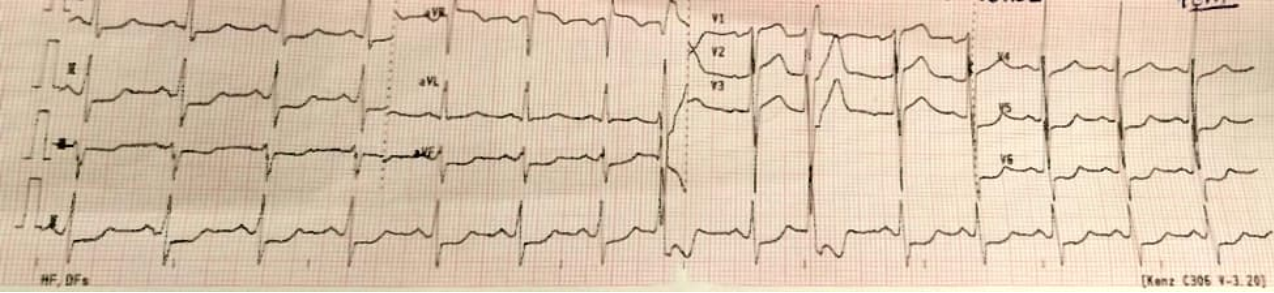

Introducción: El cierre quirúrgico de un CIV peri membranoso, puede traer como...